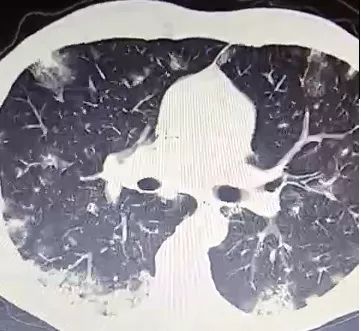

抗感染治疗,痰量增多。CT如下,没有什么特殊的。

■ 北京大学第一医院呼吸内科报道1例,每天咳痰多达500ml,外院抗感染治疗无效。给予靶向药吉非替尼治疗,痰量减少。CT如下,没有什么特殊的。

CT,双肺弥漫性病变(多发斑片、结节影、磨玻璃影),如下: